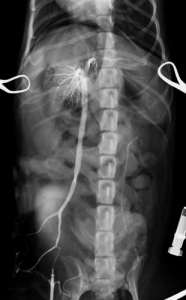

まず開腹下にて門脈造影検査と言われる特殊な血管造影検査を行い、シャント血管とレントゲン検査にて探します。今回検査にてシャント血管が左胃静脈-左横隔膜静脈を介した門脈-後大静脈シャントであることが判明しました。

左胃静脈-左横隔膜静脈を介した門脈-後大静脈シャント

完全結紮後の門脈造影検査:シャント血管の遮断が確認され、血液が完全に肝臓にいっていることが確認されました。